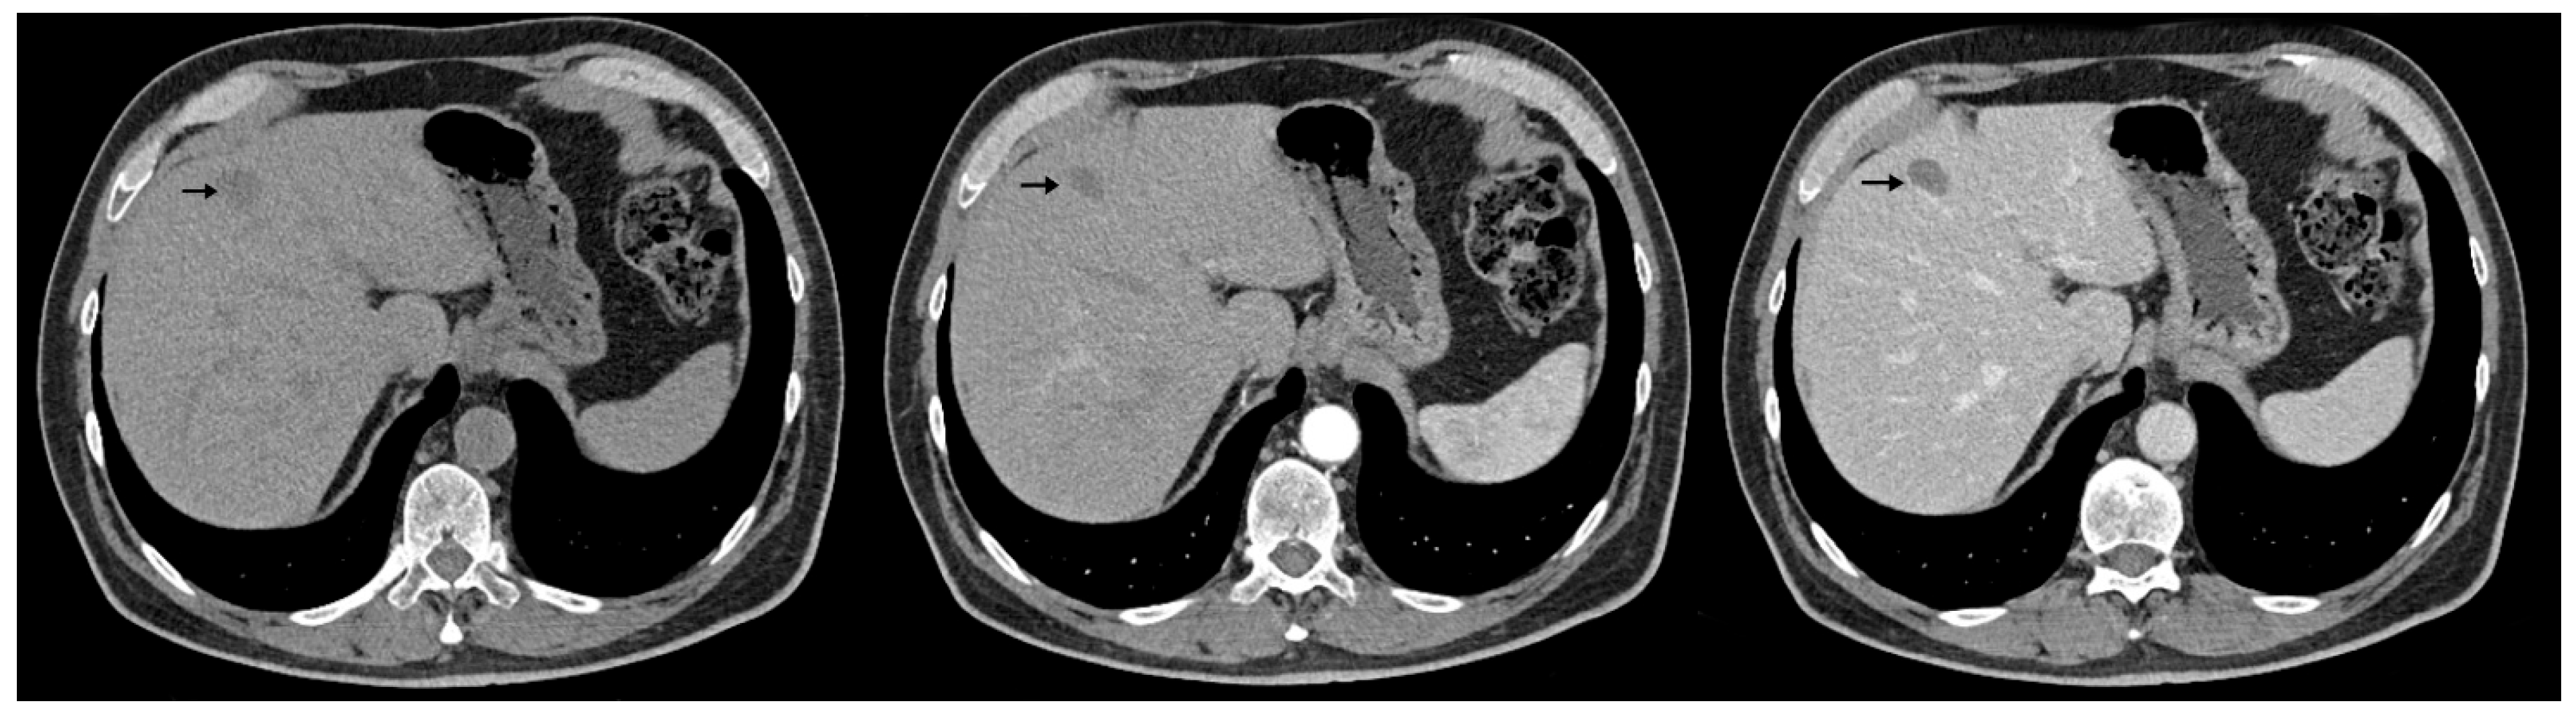

The abdominal contrast-enhanced CT scan further revealed multiple hepatic hypodense nodular lesions, measuring between 1 cm and 3 cm (Figure 6 and Figure 7).

Figure 6.

Contrast-enhanced abdominal CT (axial, non-contrast phase—left, arterial phase—center, and portal venous phase—right) shows liver sections with hypodense nodule in IVa hepatic segment exhibiting arterial-phase enhancement similar to background parenchyma and washout on the portal venous phase, measuring 1–3 cm (arrows).

Figure 7.

Contrast-enhanced abdominal CT (axial, non-contrast phase—left, arterial phase—center, and portal venous phase—right) demonstrates two hypodense hepatic nodules (black arrows) with a pseudocapsule appearance—more conspicuous on the portal venous phase—located in segments III and VIII, showing an enhancement pattern similar to Figure 6.